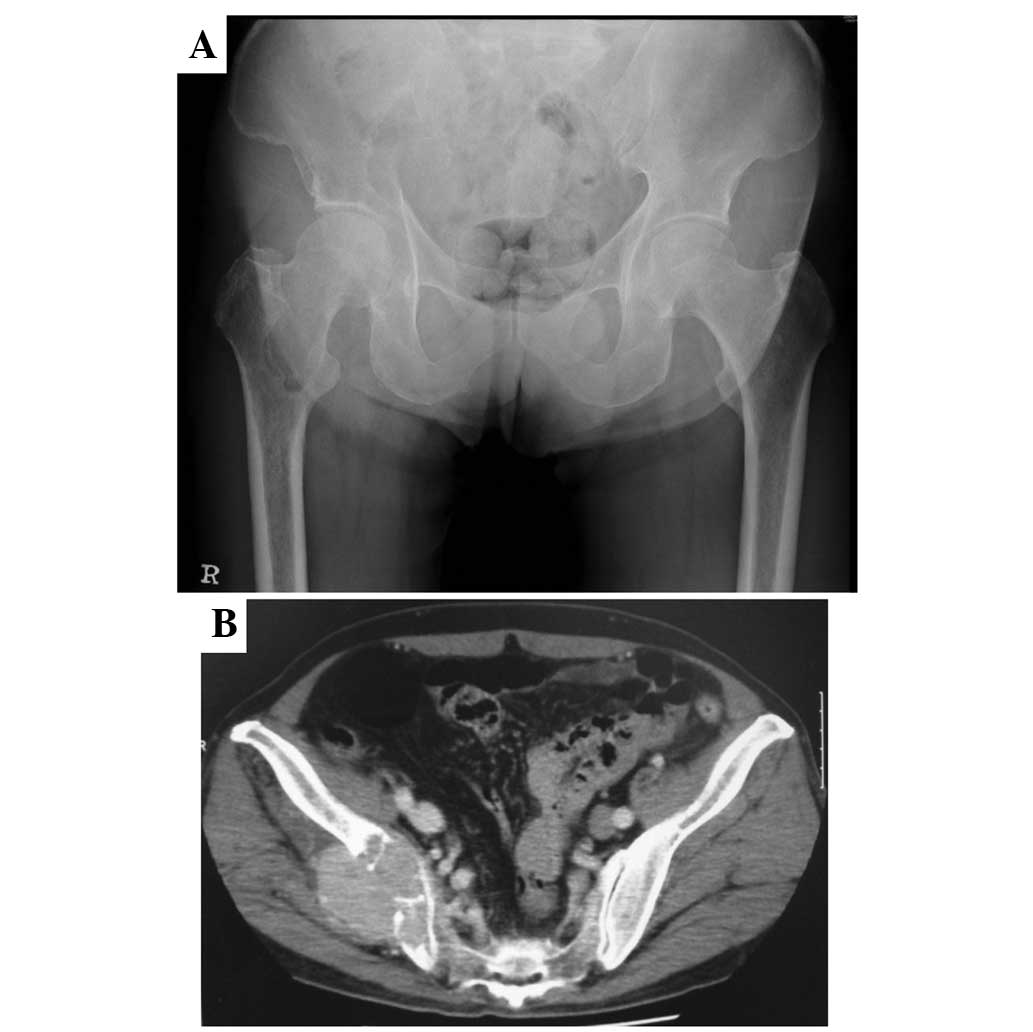

Case report demonstrating effectiveness of sorafenib in multiple lung and bone metastases of renal cell carcinoma

The current study presents the case of a 59‑year‑old male with advanced‑stage renal cell carcinoma and bone metastases in the proximal femur and ilium (cT3aN3M1; stage IV). Resection of the primary renal cell cancer and palliative surgery with a γ‑nail for an impending fracture of the right proximal femur were performed, followed by radiotherapy. Sorafenib, a multi‑kinase inhibitor that blocks the raf and tyrosine kinases of the vascular endothelial and platelet‑derived growth factor receptors, was administered for 9 months, resulting in a marked improvement in the metastatic ilium and a reduction in the extent of the lung metastases. The patient suffered minor adverse effects, including a skin rash and mild diarrhea, but remained alive at the time of follow‑up at 36 months post‑surgery. Sorafenib demonstrated efficacy against the bone metastasis of metastatic renal cell carcinoma.

Figure 1

Figure 2

Figure 3

Figure 4